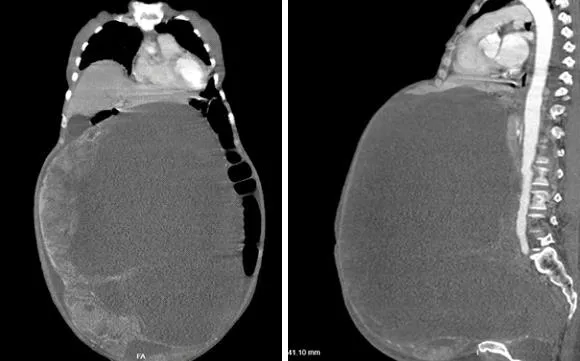

Khối u chiếm gần hết ổ bụng bà T. Ảnh: BV CUNG CẤP

Ca phẫu thuật khá khó khăn do khối u quá lớn (30 cm x 50 cm, khoảng 30 kg) và dính nhiều vào ruột, thành bụng. Tuy nhiên sau hai giờ căng thẳng, các BS cắt trọn khối u an toàn.